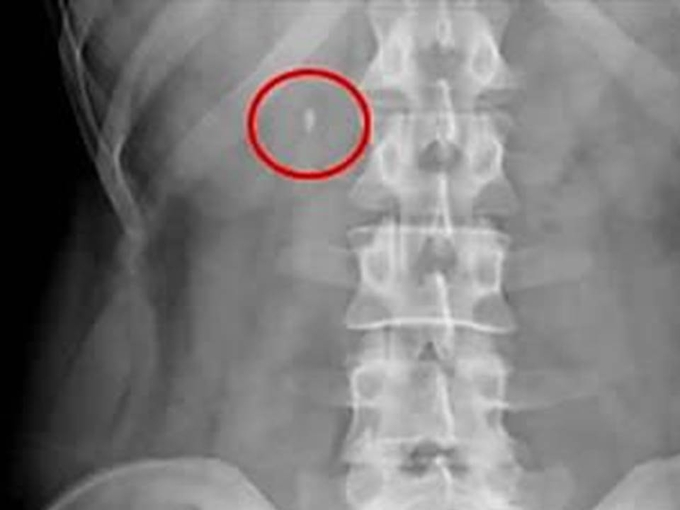

요로결석은 콩팥·요관·방광 등에 소변 속 물질이 뭉쳐 돌처럼 쌓이는 질환으로 소변에 결석을 만드는 성분이 많아질 때 생기기 쉬운데, 활동량이 늘고 기온이 올라가기 시작해 갑자기 몸속 수분이 부족해지는 봄에는 소변량이 줄고 농도가 높아져 결석이 잘 생기는 환경이 만들어진다.

요로결석의 대표 증상은 갑자기 한쪽 옆구리나 허리에 찾아오는 심한 통증이다. 통증은 아랫배나 사타구니 방향으로 내려가기도 하며, 소변에 피가 섞여 나오거나 구토 증상이 나타날 수도 있다.

이미 요로결석이 생겼다면 병원을 찾아 적절한 치료를 받아야 한다. 박 교수는 "결석의 크기가 작다면 수분 섭취·약물치료를 통한 자연 배출을, 크거나 위치가 좋지 않다면 충격파·내시경 쇄석 치료를 고려한다"고 설명했다.